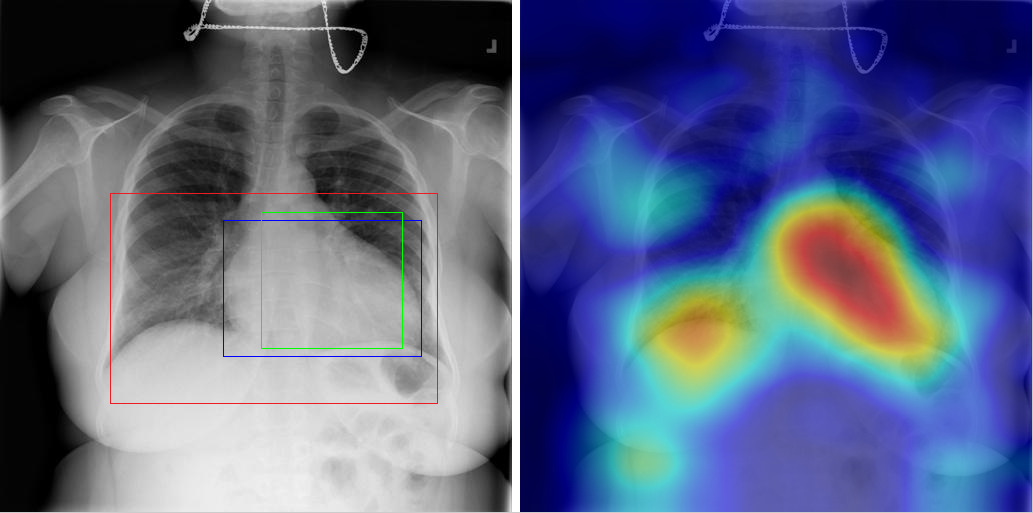

Table 8 to Table 15 illustrate localization results from each of 8 disease classes together with associated report and mined disease keywords. The heatmaps overlay on the original images are shown on the right. Correct bounding boxes (in green), false positives (in red) and the groundtruth (in blue) are plotted over the original image on the left.

In order to quantitatively demonstrate how informative those heatmaps are, a simple two-level thresholding based bounding box generator is adopted here to catch the peaks in the heatmap and later generated bounding boxes can be evaluated against the ground truth. Each heatmap will approximately results in 1-3 bounding boxes. We believe the localization accuracy and AFP (shown in Table 7) could be further optimized by adopting a more sophisticated bounding box generation method, e.g. selective search [47] or Edgebox [18]. Nevertheless, we reserve the effort to do so, since our main goal is not to compute the exact spatial location of disease patterns but just to obtain some instructive location information for future applications, e.g. automated radiological report generation. Take the case shown in Table 8 for an example. The peak at the lower part of the left lung region indicates the presence of “atelectasis”, which confer the statement of “…stable abnormal study including left basilar infilrate/atelectasis, …” presented in the impression section of the associated radiological report. By combining with other information, e.g. a lung region mask, the heatmap itself is already more informative than just the presence indication of certain disease in an image as introduced in the previous works, e.g. [42].

Radiology report Keyword Localization Result

findings: right internal jugular catheter remains in place. large metastatic lung mass in the lateral left upper lobe is again noted. no infiltrate or effusion. extensive surgical clips again noted left axilla. impression: no significant change. Mass [Uncaptioned image]

Table 12: A sample of chest x-ray radiology report, mined disease keywords and localization result from the “Mass” Class. Correct bounding box (in green), false positives (in red) and the ground truth (in blue) are plotted over the original image.